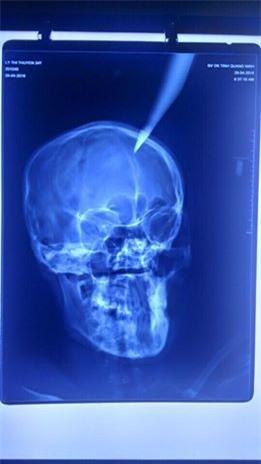

Kết quả chụp X-quang cho thấy phần đầu

nhọn của dao cắm sâu 4 cm vào não. Theo người nhà bệnh nhân, vụ tai nạn